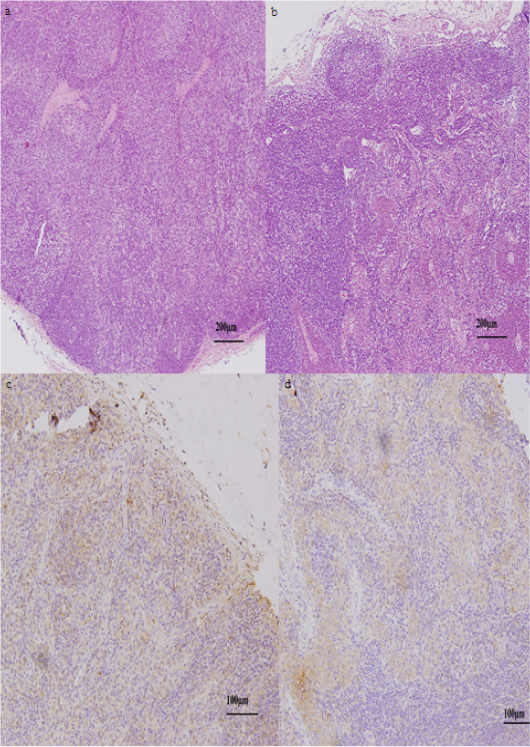

Lymph nodes of sheep at 4 hpi. (a). Normal histoarchitecture of lymphatic tissue of the control group. (b) Liquefactive degeneration found in some areas of the lymph node of the Ep group. Immunohistochemical expression in the control (c) and Ep (d) groups, (brown) as TLR4 stanning and (blue) as cells nuclei.